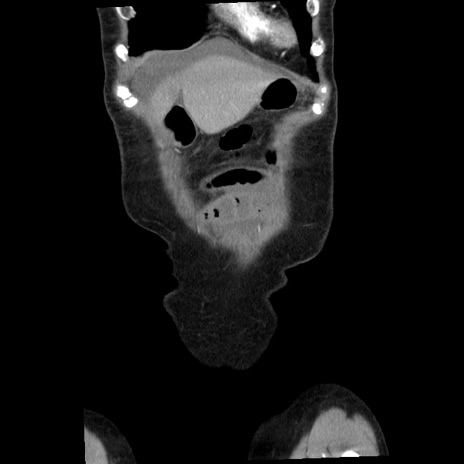

横断像

矢状断像